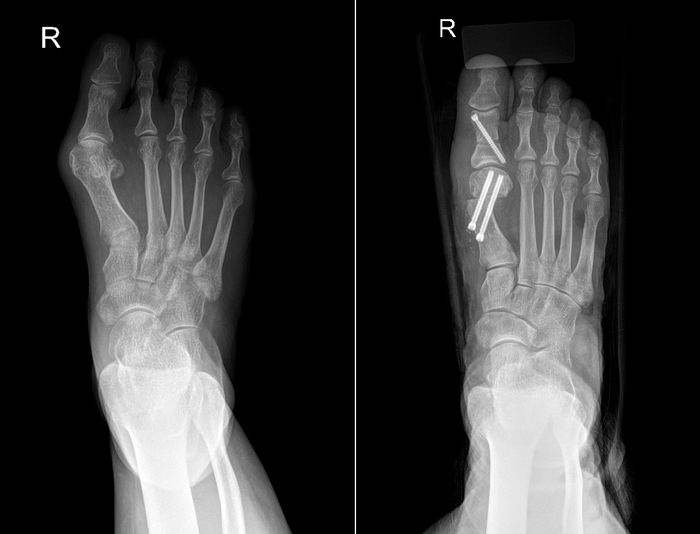

▲무지외반증 수술 전(왼쪽)과 수술 후 엑스레이 영상. 사진=바른세상병원

윤 원장은 “미카(MICA)교정술과 미타(MITA)교정술 같은 최소침습수술은 바늘 모양의 미세 절삭 기구(버, burr)를 이용해 2~3㎜ 크기의 작은 구멍을 통해 변형된 뼈를 교정하는 방식으로, 기존의 4~5㎝ 절개 방식보다 수술 시간과 회복 기간이 크게 단축된다"고 밝혔다. 미카·미타 교정술은 골막이 보존되어 뼈가 잘 아물고, 절개 부위가 작아 수술 후 통증과 흉터 부담이 모두 적다는 장점이 있다. 수술 후에는 보조기를 이용한 조기 보행이 가능하며, 빠른 일상 복귀가 가능하다.

수술 여부를 결정해야 할 때 가장 중요한 요인은 환자가 주관적으로 느끼는 불편함의 정도다. 박 교수는 “아무리 변형이 심해도 미용적인 목적을 위해 수술을 하는 것은 피해야 한다"고 했다. 무지외반증의 수술 방법은 매우 다양하고 각각의 장단점이 있기 때문이라는 것이다. 그런 만큼 환자의 나이, 변형의 심한 정도, 환자가 가장 불편하게 생각하는 부분 등을 고려해 수술 방법을 결정하게 된다. 일반적으로는 돌출 부위의 뼈를 깎아 내고 내·외측으로 치우친 뼈를 잘라서 각을 교정하며 짧아진 근육 및 연부 조직을 늘려주는 방법을 시행하게 된다.